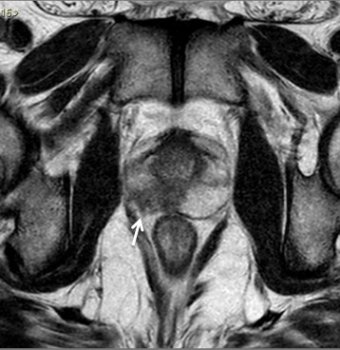

No estadiamento locorregional do câncer de próstata, o aspecto mais relevante na tomada de decisão terapêutica é a diferenciação entre tumor confinado ao órgão (T1 e T2) e tumor localmente avançado, sob as formas de extensão extracapsular (T3a) ou invasão de vesículas seminais (T3b). Para esta avaliação, as imagens ponderadas em T2 são as mais indicadas15,18(fig. 5 e 6).

Figura 5. Estadiamento de adenocarcinoma de próstata Gleason 7. Imagem ponderada em T2 evidencia nódulo no terço médio da zona periférica direita, notando-se pequena irregularidade da cápsula prostática adjacente à lesão, sugestivo de extensão extra-capsular.

Figura 6. Estadiamento de adenocarcinoma da próstata Gleason 9. A) Lesão hipointensa comprometendo quase toda a glândula, com extensão para a gordura periprostática à direita. B) Comprometimento das vesículas seminais.

Os critérios de imagem para extensão extracapsular incluem assimetria ou envolvimento macroscópico dos feixes neurovasculares, abaulamento focal do contorno prostático, espiculação ou irregularidade do contorno prostático, obliteração do ângulo retoprostático, retração capsular, e sinais de rotura capsular com extensão direta a gordura periprostática. Lesões que exibem contato maior que 1,0 cm com a cápsula prostática apresentam maior risco de extensão extracapsular.15,18

Os achados que indicam invasão das vesículas seminais incluem: aumento de tamanho, assimetria e hipointensidade das vesículas seminais, obliteração do ângulo vesicoprostático e extensão direta da base prostática à vesícula seminal, sendo este achado o de maior valor preditivo positivo.15,18